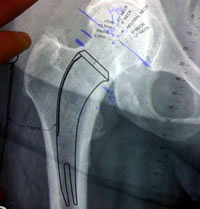

The MiniHipTM Stem from Corin has followed a similar path as that of the CFPTM Pipino Stem and the ARCTM and MSATM Tissue Sparing Implants. All are curved neck stabilized stems.

All four of these designs rely on neck stabilization not like typical short stems than rely on metaphyseal stabilization.

| The medial curve of the calcar is the key to neck stabilized stem designs. |

| Pre-op templating |

His own templating process |

Determining neck resection |